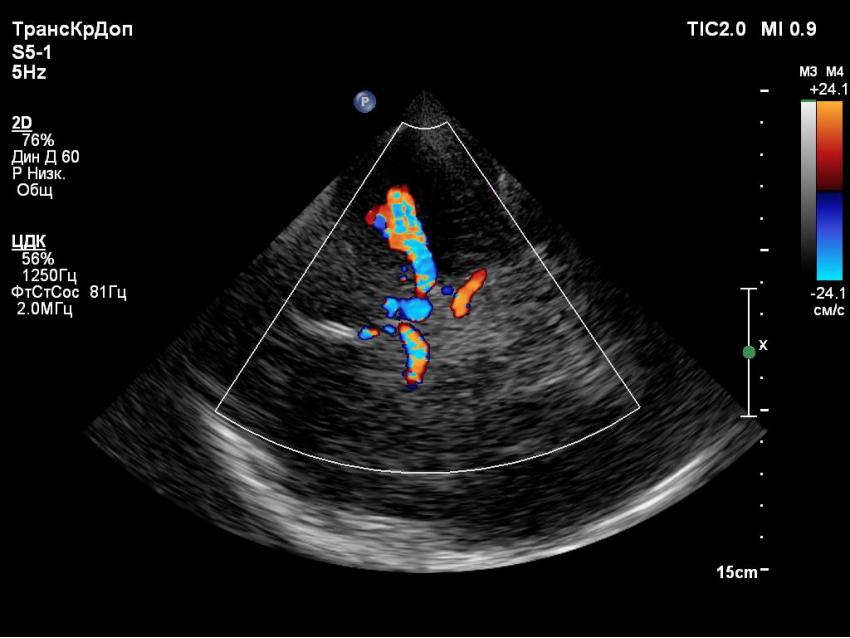

The examination is performed with a sector transducer through 'cranial windows', as these are the areas where bones of the skull are thinner and allow the best transmission of ultrasound. On the side of device, a good penetrating ability is provided by a stream of waves with low frequency. Since the higher the frequency, the faster the ultrasound wave attenuates, it is best to use transducers with a frequency of 1-6 MHz.

However, in order to obtain a diagnostically-appropriate image, one sensor with the appropriate frequency is not enough. You also need a machine with a good power which allows us to obtain an image with acceptable 2D resolution and high color Doppler sensitivity. We all know that machines are divided into different classes. In this article, we want to show you that for a good head vascular examination, it is not necessary to choose a premium class machine with an exorbitant price.

They are proven to be expert class machines that demonstrate their ability in all types of examinations. This image is from Toshiba Aplio 300. Generally speaking, the wide range of functions of this company's machines allows us to achieve the image option that best suits the doctor. Those who have encountered images from different brands will understand.